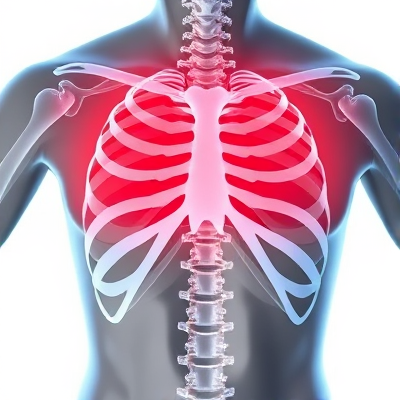

왼쪽 갈비뼈 위통증, 원인과 대처방법은 무엇일까요?

왼쪽 갈비뼈 위통증, 무엇이 원인일까요?

왼쪽 갈비뼈 위통증, 어떤 원인이 있을까요?

왼쪽 갈비뼈 위통증의 원인은 생각보다 다양합니다. 가장 흔한 원인은 자세 문제와 근육 경직, 그리고 디스크 질환입니다. 오랜 시간 구부정한 자세로 있다 보면 척추와 근육이 뭉치면서 통증이 생길 수 있죠. 또한 목 디스크나 등 디스크 문제도 왼쪽 갈비뼈 부위 통증으로 나타날 수 있습니다.

이 외에도 심장 질환, 췌장 질환, 폐 질환 등 내부 장기 문제로 인해 통증이 발생할 수 있습니다. 특히 심장 협심증이나 대동맥 박리 등은 왼쪽 가슴 부위에 통증을 유발하므로 주의해야 합니다. 또한 요로결석이나 신우신염 등 비뇨기 질환도 이 부위 통증의 원인이 될 수 있습니다.